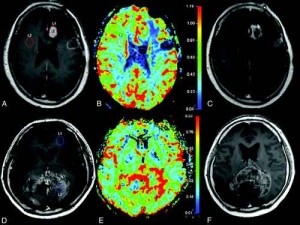

Una terapia multipla sembra essere efficace nell'aumentare la sopravvivenza al glioblastoma, un grave tumore del cervello. L'esperimento, finora eseguito solo...